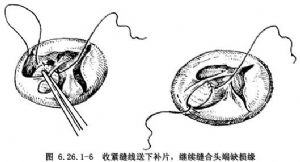

連續縫合補片修復法:由右房經三尖瓣口先於缺損12點部位,用4-0聚丙烯縫線做一單純縫合,補片修剪成略大於室間隔缺損(圖6.26.1-5),縫數針後拉緊縫線,將補片下送到位,繼續向頭端肌肉緣縫合(圖6.26.1-6左),牽拉縫線顯示下一步縫合區,抵達上方心室漏斗褶肌緣和三尖瓣環結合部後,縫線穿過三尖瓣前瓣基底部,自心室至心房側,隨後從心房回至心室側,穿過補片緣,收緊縫線(圖6.26.1-6右)。用另一頭縫線從缺缺損下緣往後繼續連續縫合(圖6.26.1-7左),到後下緣時縫線應離開缺損邊緣5mm,從間隔右室面進出針,切勿穿過間隔組織,以防損傷希氏束(圖6.26.1-7右)。兩針於相遇處結紮,閉合缺損。